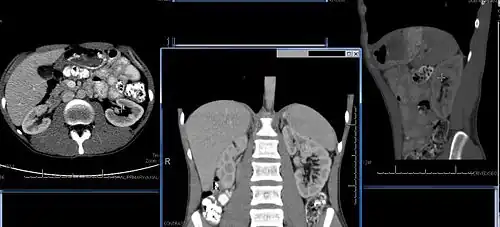

Chronic kidney disease (CKD) has been recognized as a leading public health problem worldwide. The global estimated prevalence of CKD is 13.4%, and patients with kidney failure needing renal replacement therapy are estimated between 5 and 7 million.[6] Procedures used in the management of kidney disease include chemical and microscopic examination of the urine (urinalysis), measurement of kidney function by calculating the estimated glomerular filtration rate (eGFR) using the serum creatinine; and kidney biopsy and CT scan to evaluate for abnormal anatomy. Dialysis and kidney transplantation are used to treat kidney failure; one (or both sequentially) of these are almost always used when renal function drops below 15%. Nephrectomy is frequently used to cure renal cell carcinoma.

Normal adult right kidney as seen on abdominal ultrasound with a pole to pole measurement of 9.34 cm -

Renal ultrasonography is essential in the diagnosis and management of kidney-related diseases.[49] Other modalities, such as CT and MRI, should always be considered as supplementary imaging modalities in the assessment of renal disease.[49]